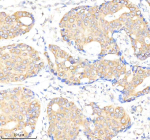

IHC analysis of FFPE human breast carcinoma tissue stained with the ALK3 antibody

IHC (Paraffin) : 1:50-1:100